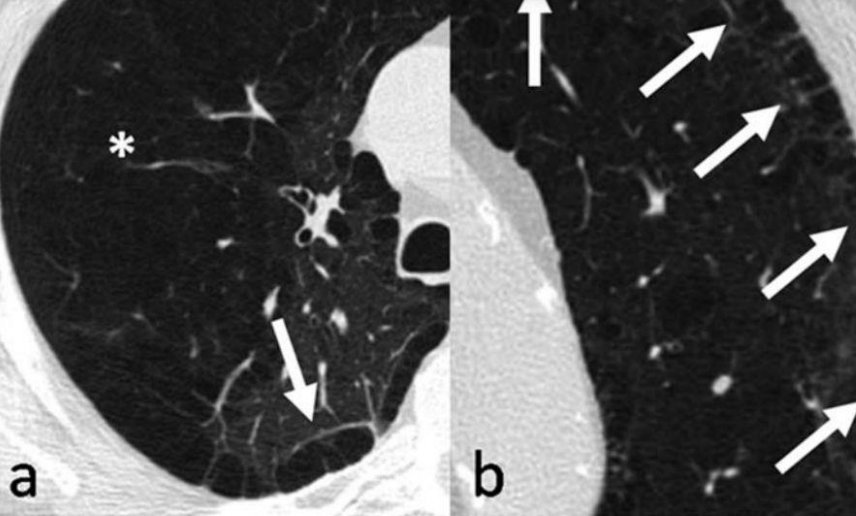

Permite clasificar: centrolobulillar, panlobulillar, paraseptal

Centrolobulillar

Paraseptal